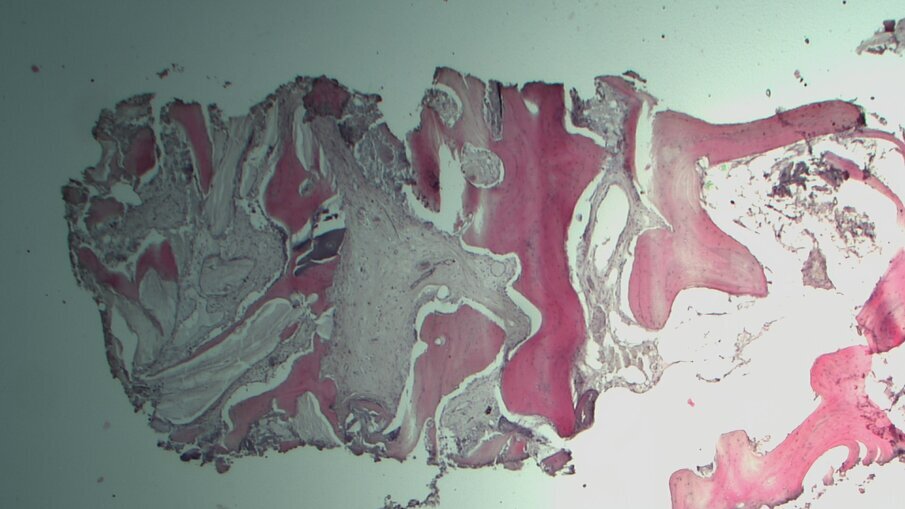

Quattro pazienti con severa atrofia verticale dell’osso alveolare della regione posteriore del mascellare superiore, che necessitavano di una riabilitazione implantoprotesica unilaterale della zona edentula, sono stati trattati con la tecnica del Sinus Pack. Dopo 6 mesi è stata eseguita una TC per valutare il volume osseo ottenuto, sono stati inseriti gli impianti ed è stata inoltre prelevata una carota ossea di 4 mm con una fresa carotatrice ossea. Sono stati sottoposti a trattamento tre uomini e una donna (range di età tra 36 e 74 anni); non sono state registrate complicanze intra o postoperatorie. Confrontando le misurazioni eseguite sulla TC preoperatoria e dopo 6 mesi dall’intervento, è stato riscontrato un guadagno verticale di osso pari a 6,95 mm (Figg. 1-4). Nella valutazione dell’analisi istologica e istomorfometrica della carota ossea prelevata si è riscontrato un completo riassorbimento della membrana, una neoformazione ossea e solo una piccola percentuale di innesto ancora presente (Figg. 5-7).